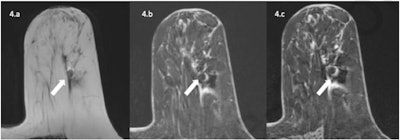

A 63-year-old patient with invasive ductal carcinoma marked by an Ultraclip metallic marker and treated with neoadjuvant chemotherapy underwent a preoperative 1.5T MRI exam with T2-weighted, 3D T1-weighted VIBE before and after contrast media injection. Metallic marker is responsible for a hypointense artifact with hyperintense halo more important with fat saturation than Dixon sequences as expected. Because of this artifact, the patient was considered Radiological Complete Response (rCR) with low diagnostic confidence from both readers, but residual tumor was detected in final pathology results.

A 63-year-old patient with invasive ductal carcinoma marked by an Ultraclip metallic marker and treated with neoadjuvant chemotherapy underwent a preoperative 1.5T MRI exam with T2-weighted, 3D T1-weighted VIBE before and after contrast media injection. Metallic marker is responsible for a hypointense artifact with hyperintense halo more important with fat saturation than Dixon sequences as expected. Because of this artifact, the patient was considered Radiological Complete Response (rCR) with low diagnostic confidence from both readers, but residual tumor was detected in final pathology results.The authors' hope was that the clips were not responsible for a decrease in the diagnostic accuracy of MRI, which would have called into question the interpretation of post-NAC breast MRI, Hugot explained.